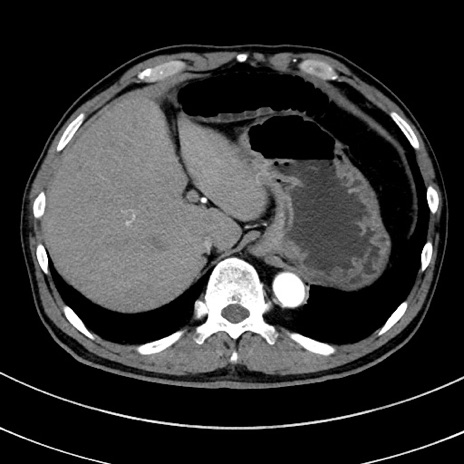

症例8(横断像)

【症例】 60歳代男性

【主訴】 黒色吐物

【現病歴】 4日前から嘔気自覚、2日前の朝食後にも嘔気あり、自分で手で嘔吐反射起こし嘔吐したところ血が混ざっていたため受診。

【既往歴】 5年前汎発性腹膜炎を伴う急性虫垂炎で手術、高血圧、前立腺肥大症、高脂血症

【身体所見】 腹部正中に手術癩痕あり 腹部平坦・軟圧痛なし膨満感あり

【データ】WBC 8400、CRP 4.54